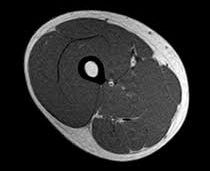

Magnetic resonance imaging (MRI)

The MRI requires an individual to lay flat on a motorized bed which is then moved into a large cylindrical scanner which is open at both ends. The MRI creates a magnetic field which causes all the spinning protons in our body to align with the magnetic field, the stronger this magnetic field the more detailed the image will be, radio waves are then sent through the body and it’s weak magnetic field disrupts the protons and they gain energy, the radio waves are then turned off and the protons go back into alignment with the magnetic field, this releases energy, a coil is placed around the particular body part and it measures the emitted energy, from this a computer image of the cross-sectional area of the scanned body part is generated, as different tissues contain different amounts of water, and each water molecule contains 2 protons which release the energy, so the types of tissue in the scanned area can be gathered. This process takes 15-90 minutes. Sometimes an individual may need a contrast dye to be able to enhance the differences between tissues, this can be injected, drank or enter the body through an enema before the test.

MRI of the thigh:

The MRI is noninvasive, it doesn’t produce any ionising radiation and it is a very accurate method for judging body composition, and this is why the other methods of judging body composition are usually judged in comparison to the MRI, as it often estimates muscle mass correctly within 7.5%. However, getting an MRI scan is expensive, time-consuming and the accuracy of the MRI can be compromised when trying to gather information on muscles in close proximity of others or for muscles with multiple heads, for this reason, the volume for smaller muscles is often underestimated, likely due to a lack of samples taken along the muscles. Muscles with a large ratio of surface area to volume are particularly hard to judge the muscle mass of. An MRI can be used to take samples all around the body and find an individual’s whole-muscle volume, but the MRI is best used to find the muscle volume of certain body parts.